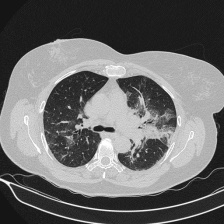

COVID Detection: Challenge that aims to classify lungs between COVID and non-COVID classes. The dataset for this challenge is unbalanced, having 922 CT scans affected by COVID-19, and 2110 healthy ones, while in the validation set, these values are 225 and 489, respectively. Figure 1 shows a diagram of the layout of the images made available for this challenge, whereas Figure 2 illustrates some examples of images of the COVID and non-COVID classes.

Figure 2: Examples of CT images from the MIA-COV19D database. Each of the images corresponds to one of the tomography slices, of lungs affected (for instance, (a) and (b)) or not by COVID-19 (for instance, (c) and (d)).